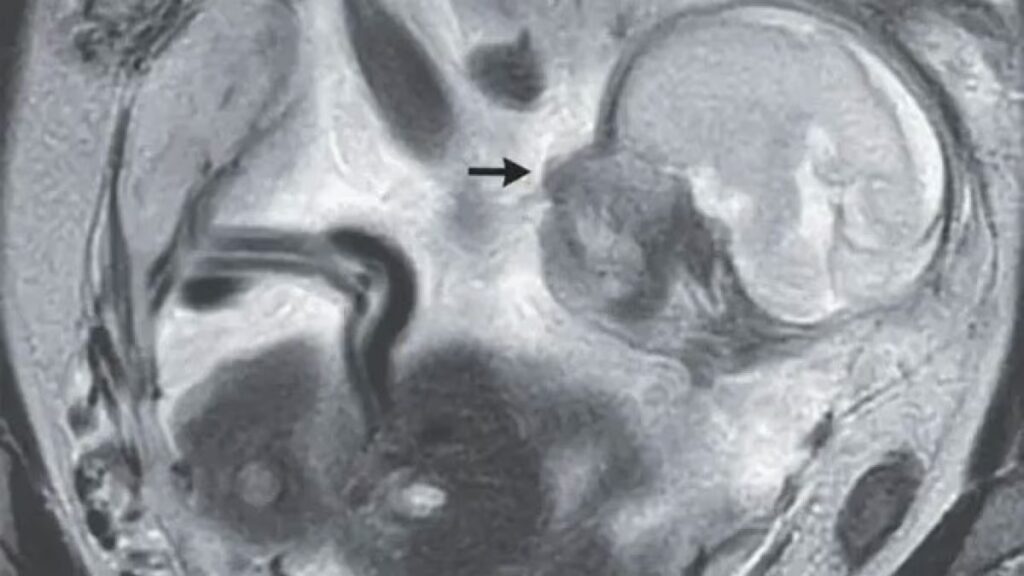

I risultati ottenuti sono straordinari: una bambina affetta da atrofia muscolare spinale (Sma) è stata trattata con una terapia innovativa mentre era ancora nella pancia della madre. Oggi, a distanza di due anni e mezzo dalla nascita, la piccola non presenta alcun sintomo.

Tale ricerca è stata effettuata grazie ad un farmaco, il risdiplam, somministrato alla madre quando era incinta e in grado di agire sulla componente genetica della malattia.

Alla nascita della bambina gli esami hanno confermato la precedente diagnosi di Sma, ma hanno anche sottolineato come il farmaco somministrato in gravidanza avesse raggiunto il feto.

La bambina, infatti, non presentava alcun sintomo già al momento della nascita.